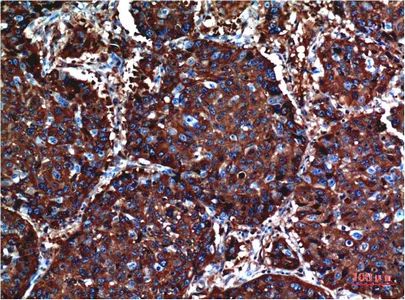

AKT(10D6)Mouse Monoclonal Antibody

Cat: AMM06739

Size1:50μl Price1:$128

Size2:100μl Price2:$230

Size3:500μl Price3:$980